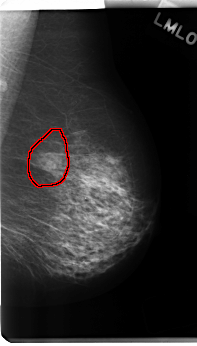

C_0228_1.LEFT_MLO

LEFT_MLO LINES 4832 PIXELS_PER_LINE 2752 BITS_PER_PIXEL 12 RESOLUTION 50 OVERLAY

FILE: C_0228_1.LEFT_MLO.OVERLAY

TOTAL_ABNORMALITIES 1

ABNORMALITY 1

LESION_TYPE MASS SHAPE OVAL MARGINS ILL_DEFINED

ASSESSMENT 4

SUBTLETY 3

PATHOLOGY MALIGNANT

TOTAL_OUTLINES 1

BOUNDARY